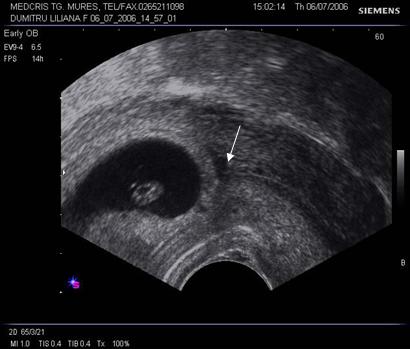

Fig nr. 67 Decolare de pol inferior ovular, situat in continuarea canalului cervical

( sageata) la ecografia transvaginala